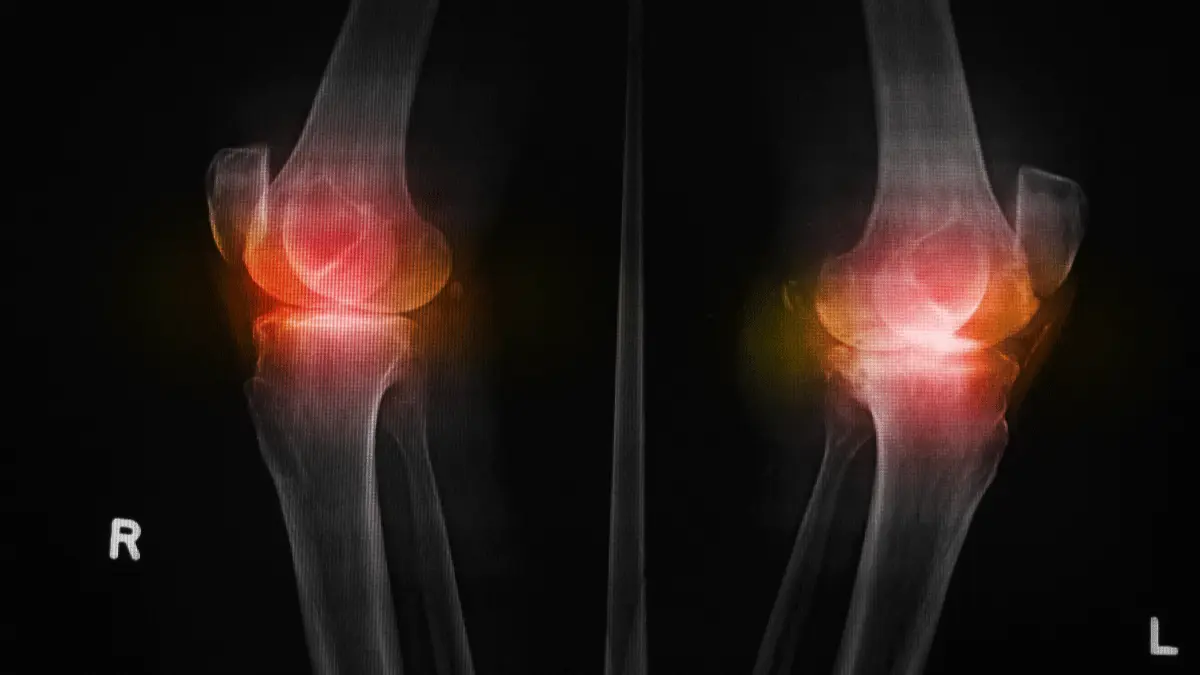

Essa preocupação é completamente compreensível e natural, afinal, estamos falando de uma cirurgia de grande porte que vai alterar definitivamente a estrutura de uma das articulações mais importantes do nosso corpo.

A dor após a colocação de uma prótese de joelho é, na verdade, muito menos intensa do que a dor que o paciente sentia antes da cirurgia. Essa é uma das primeiras informações que compartilho com meus pacientes durante a consulta inicial.